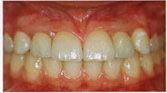

- Podrá hablar, reír y sonreír sin

preocuparse por sus nuevos dientes : están firmemente anclados y los sentirá

igual que si fueran sus propios dientes.

- Recuperará su sonrisa natural.

Los implantes dentales nos permitirán masticar con total comodidad, sonreír y hablar con la misma seguridad que con nuestros propios dientes.

Mucha gente que ha perdido dientes encuentra difícil poder duplicar la función y estética con prótesis removibles. Hoy en día los Implantes Dentales vienen a ofrecer una solución que se acerca más a volver a tener dientes naturales. Ya sea que usted tenga dentaduras totales o puentes parciales, los Implantes Dentales pueden ser una opción y cambio favorable del estado general de su boca.